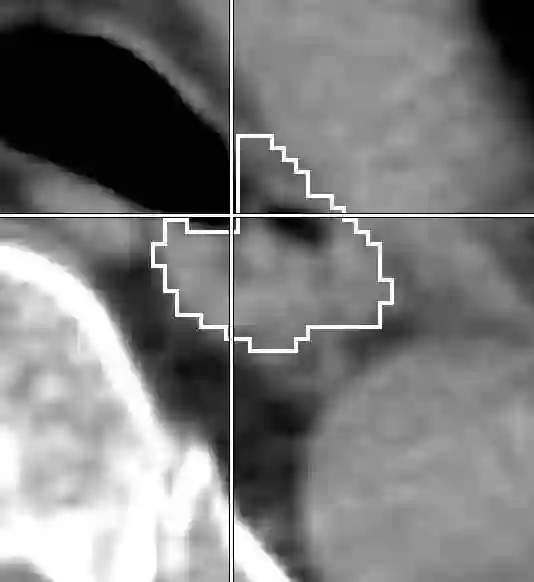

Stereotactic body radiation therapy allows for a precise and accurate dose delivery. Organ motion during treatment bears the risk of undetected high dose healthy tissue exposure. An organ very susceptible to high dose is the oesophagus. Its low contrast on CT and the oblong shape renders motion estimation difficult. We tackle this issue by modern algorithms to measure the oesophageal motion voxel-wise and to estimate motion related dosimetric impact. Oesophageal motion was measured using deformable image registration and 4DCT of 11 internal and 5 public datasets. Current clinical practice of contouring the organ on 3DCT was compared to timely resolved 4DCT contours. The dosimetric impact of the motion was estimated by analysing the trajectory of each voxel in the 4D dose distribution. Finally an organ motion model was built, allowing for easier patient-wise comparisons. Motion analysis showed mean absolute maximal motion amplitudes of 4.24 +/- 2.71 mm left-right, 4.81 +/- 2.58 mm anterior-posterior and 10.21 +/- 5.13 mm superior-inferior. Motion between the cohorts differed significantly. In around 50 % of the cases the dosimetric passing criteria was violated. Contours created on 3DCT did not cover 14 % of the organ for 50 % of the respiratory cycle and the 3D contour is around 38 % smaller than the union of all 4D contours. The motion model revealed that the maximal motion is not limited to the lower part of the organ. Our results showed motion amplitudes higher than most reported values in the literature and that motion is very heterogeneous across patients. Therefore, individual motion information should be considered in contouring and planning.